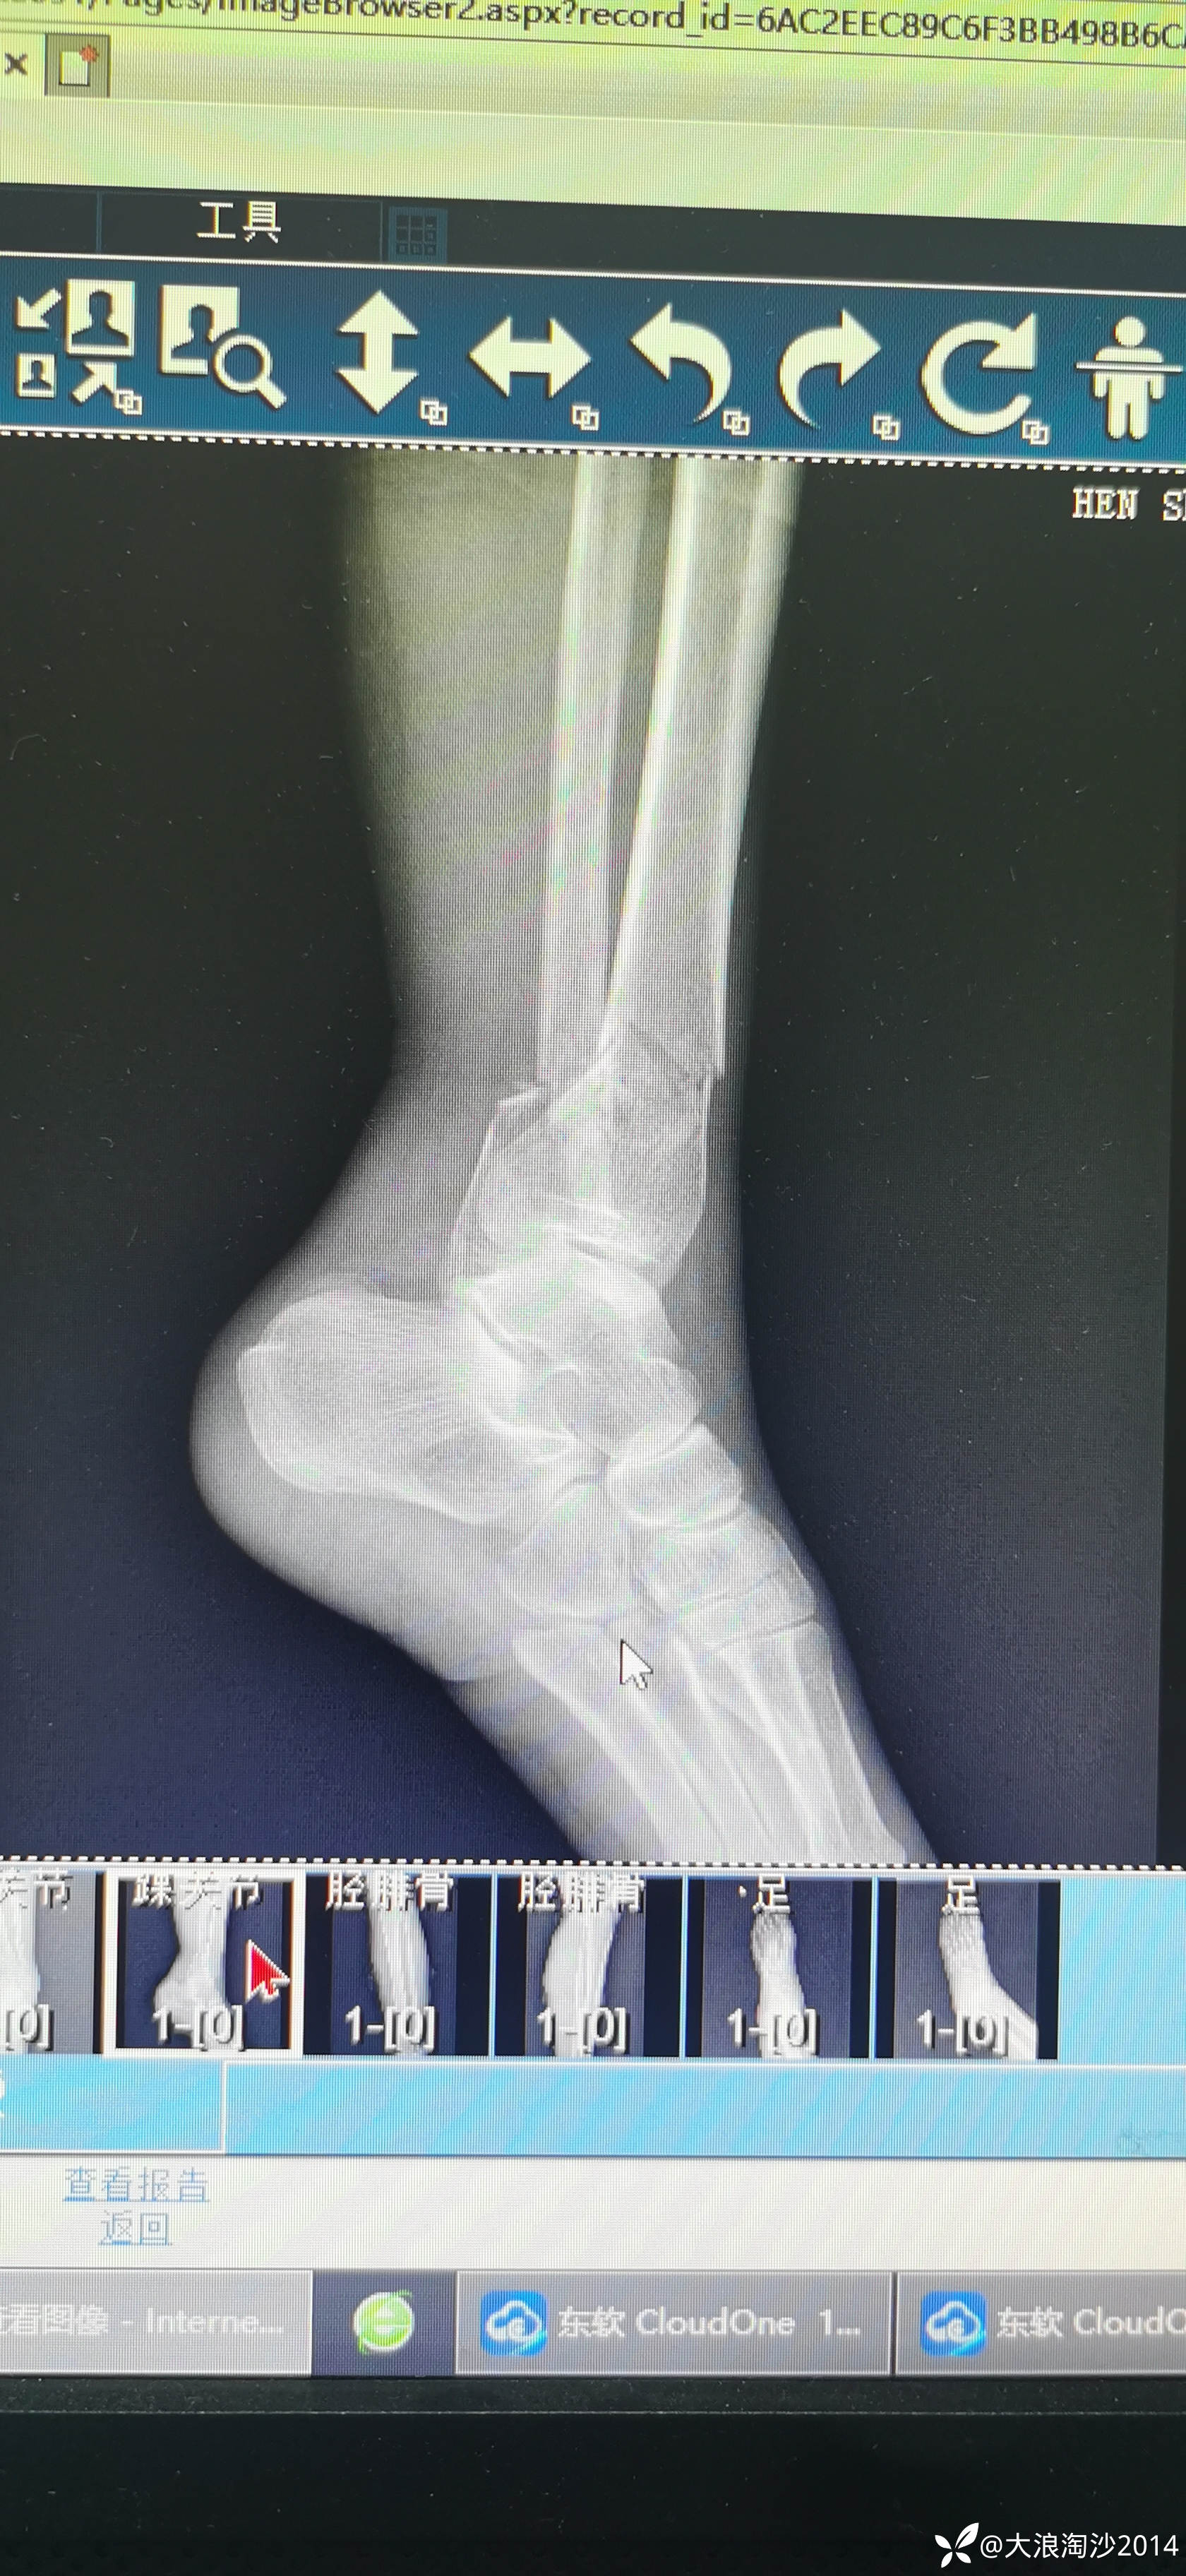

一65岁女性患者,偏瘦,体重75斤,车祸外伤致左胫腓骨远端骨折,入院后消肿后,病人可以用皮包骨头形容,考虑胫骨远折端不适合用内侧插板(mippo技术),病人太瘦,如取两个切口分别处理胫腓骨,切口容易出现问题,因此采用前外侧一个切口处理胫腓骨远端骨折(片子顺序上传有点乱)